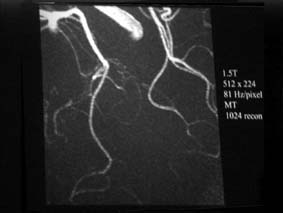

| 112: 3TのTOF MRA拡大像.ーおお,これはかなり分解能高いぞ!(片田) | 113: 1.5TのTOF MRA拡大像 |